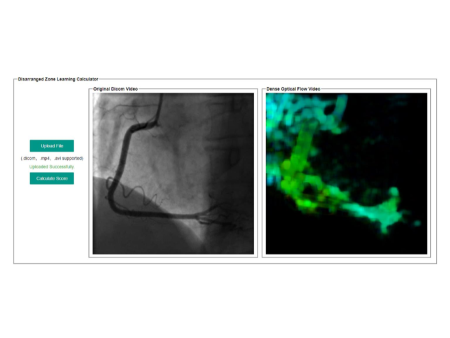

5.4 Software Implementation

We implemented DZL methodology and developed a software to generate SCOREs for any right coronary angiography in DICOM, AVI and MP4 forms. The software interface is as Figure 13. From Figure 14, the left side RCA coronary angiography uploaded in our example is an abnormal video with occlusion while the right side RCA coronary angiography uploaded in our example is a normal segment. The final SCOREs are calculated as Figure 14, the occlusion video gets 0.77 and the normal video gets 0.85. You can find the DZL calculator on http://47.103.11.61/DisarrangedZoneLearningCalculator/

Refer to caption

Figure 13: Software Interface

Figure 14: Scores Generation. The left RCA coronary angiography uploaded in our example is an abnormal video with occlusion while the right RCA coronary angiography uploaded in our example is a normal video. The final SCOREs are calculated: the occlusion video gets 0.77 and the normal video gets 0.85.